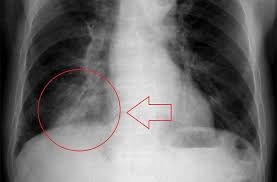

Bạn đã bao giờ tận mắt nhìn thấy hình ảnh bệnh viêm phổi khiến giới y học rúng động chưa? Những bức hình chụp X-quang, CT ngực cho thấy phổi trắng xóa, tổn thương nặng nề và lan rộng như một cơn bão trong lồng ngực. Chúng không chỉ gây sốc cho người xem mà còn cảnh báo mức độ nguy hiểm của căn bệnh này – thứ có thể cướp đi sinh mạng trong tích tắc nếu không điều trị kịp thời.

Bộ sưu tập hình ảnh bệnh viêm phổi dưới đây không dành cho người yếu tim – từng tấm ảnh như một lời cảnh báo trực quan về sức tàn phá của vi khuẩn, virus trong phổi. Từ những mảng mờ đục lan rộng đến khoang phổi sưng viêm dữ dội, tất cả hiện lên rõ nét, khiến bất cứ ai cũng phải giật mình và quan tâm hơn đến việc bảo vệ sức khỏe hô hấp của mình.